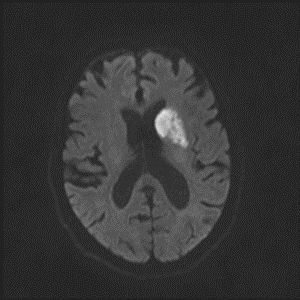

8/ Next evening, patient does the same thing, NIHSS=8, word-๐Ÿฅ—, worsening right hemiparesis. #Strokealert again and CT with new stroke noted. BP at this time 110s:

9/ CTA/P completed as well. LM1 thrombus now appears <occlusive (note that calcification makes vessel appear >open than it actually is), CTP without clear penumbra, but TMax high in posterior MCA division.